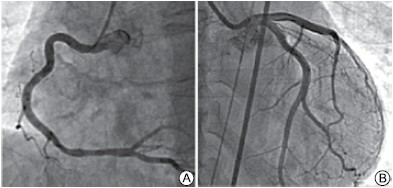

Mulher, 75 anos, apresenta dor torácica de forte intensidade após o falecimento do marido. É levada ao serviço de emergência onde eletrocardiograma mostra supradesnivelamento do segmento ST de V1 a V6. Encaminhada para hemodinâmica que mostra os seguintes achados:

Coronárias:

(Arquivo pessoal; imagens usadas com autorização)

Assinale a alternativa com o diagnóstico correto.